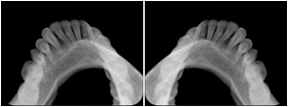

2. A patient requests cosmetic surgery to enhance their facial appearance. The case requires consultation between an orthodontist in New York and an oral surgeon in California. The cephalometric series of 2D projections constructed from a volumetric CT data set that is used for the discussion is arranged by a Structured Display for transfer between the two practitioners.

Cephalometric Series Structured Display

Figure OO-2. Cephalometric Series Structured Display